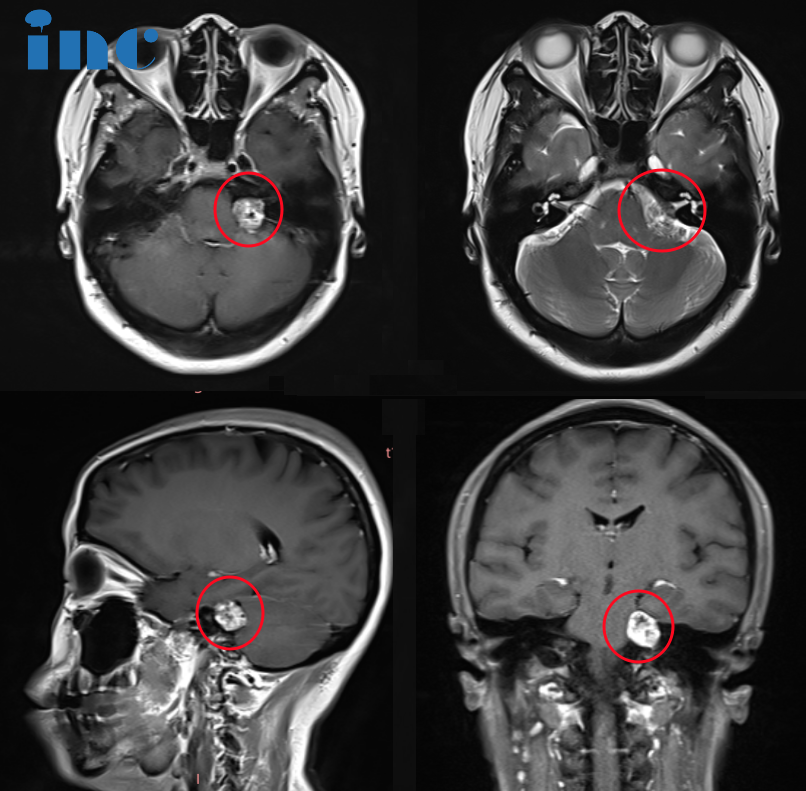

43岁女士--脑干海绵状血管瘤合并出血

2023年的1月,陶女士由于右侧嘴角发麻到医院查出脑干海绵状血管瘤、且脑干部位渗血。当地医院建议手术治疗。北京多家医院就诊,给出的建议都是保守治疗。原因是症状轻,位置深,手术风险大,建议等二次出血后再行手术。回家保守观察后,没有任何治疗,直到10月17日晚,陶女士再次感觉到麻胀感延伸到整个身体。10月再次增强核磁检查,提示再次出血,病灶从原本的1.2cm增大到1.6cm。1年内2次出血,病灶也在增大,现在需要手术吗?陶女士开始焦虑起来……

巴教授是如何为她评估的:“较佳手术时间就是是现在。原因是随着出血脑干会被血肿压迫膨胀,从而形成更大的手术空间,手术的话对周围的颅神经损伤风险会降低。但是随着血肿逐渐被吸收,局部瘢痕组织形成会导致手术难度翻倍增大,这会给患者带来更大的手术风险。在这个位置现在存在大量的血肿,经过手术可以给这个血肿清除掉。我可以为患者提供手术,将脑干海绵状血管瘤完全切除,并且在不出现面瘫的情况。她需要尽快赶往苏州,因为几天后我将会抵达此次中国之行的二站——苏州。”